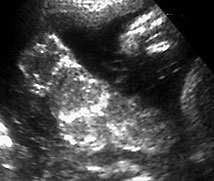

Normal appearing posterior fossa (normal size<1.0 cm from vermis of cerebellum to occipital bone inner edge).